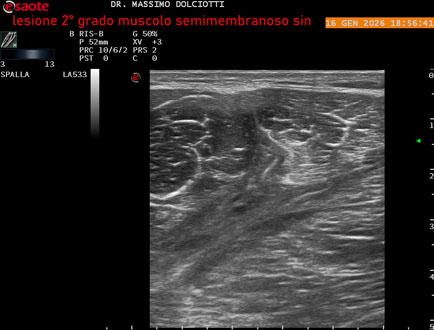

Data inserimento: 23/01/2026

Ecografia del: 16/01/2025

Età Paziente: M 23 anni

Motivazione dell'esame: dolore coscia sinistra da tre giornii.

Commento all'esame: le immagini ed il video documentano il muscolo semimembranoso sinistro disomogeneo per area iso-ipoecogena delle dimensioni di 38 x 14,7 mm per asse corto trasversale, 81 x 22 mm per asse longitudinale, come da lesione di 2° grado, con minimo versamento siero-ematico intramuscolare.

Conclusioni: lesione di 2° grado del muscolo semimembranoso sinistro (2nd degree lesion of the left semimembranosus muscle).